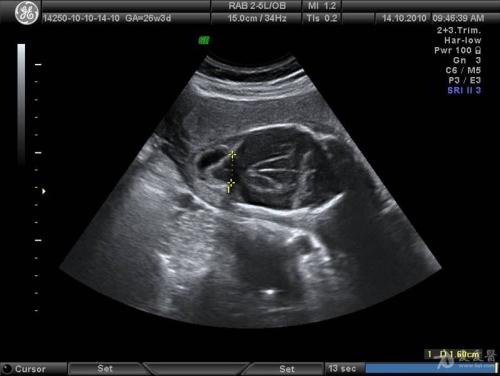

超声检查显示:宫内妊娠20 周,臀位,最大羊水深度2cm,羊水指数(AFI) 4cm,胎儿双肾、膀胱、胃泡显示欠清。

在B超的第二次检查中,结果和第一次一样,胃泡、膀胱未显示,可探及双肾动脉血流,双肾偏大,回声偏强。

最后,小周同意了姜医生的意见,以米非司酮+米索前列醇药物进行了引产。一天后顺娩一死男胎,外观无明显畸形,羊水极少。胎儿尸体解剖报告提示胎儿双肾增大,病理报告:双肾增大,双肾实质内集合管囊状扩张,符合婴儿型多囊肾改变。